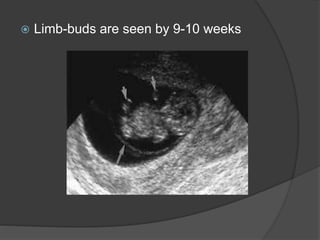

 Limb-buds are seen by 9-10 weeks

 Limb-buds areseen by 9-10 weeks